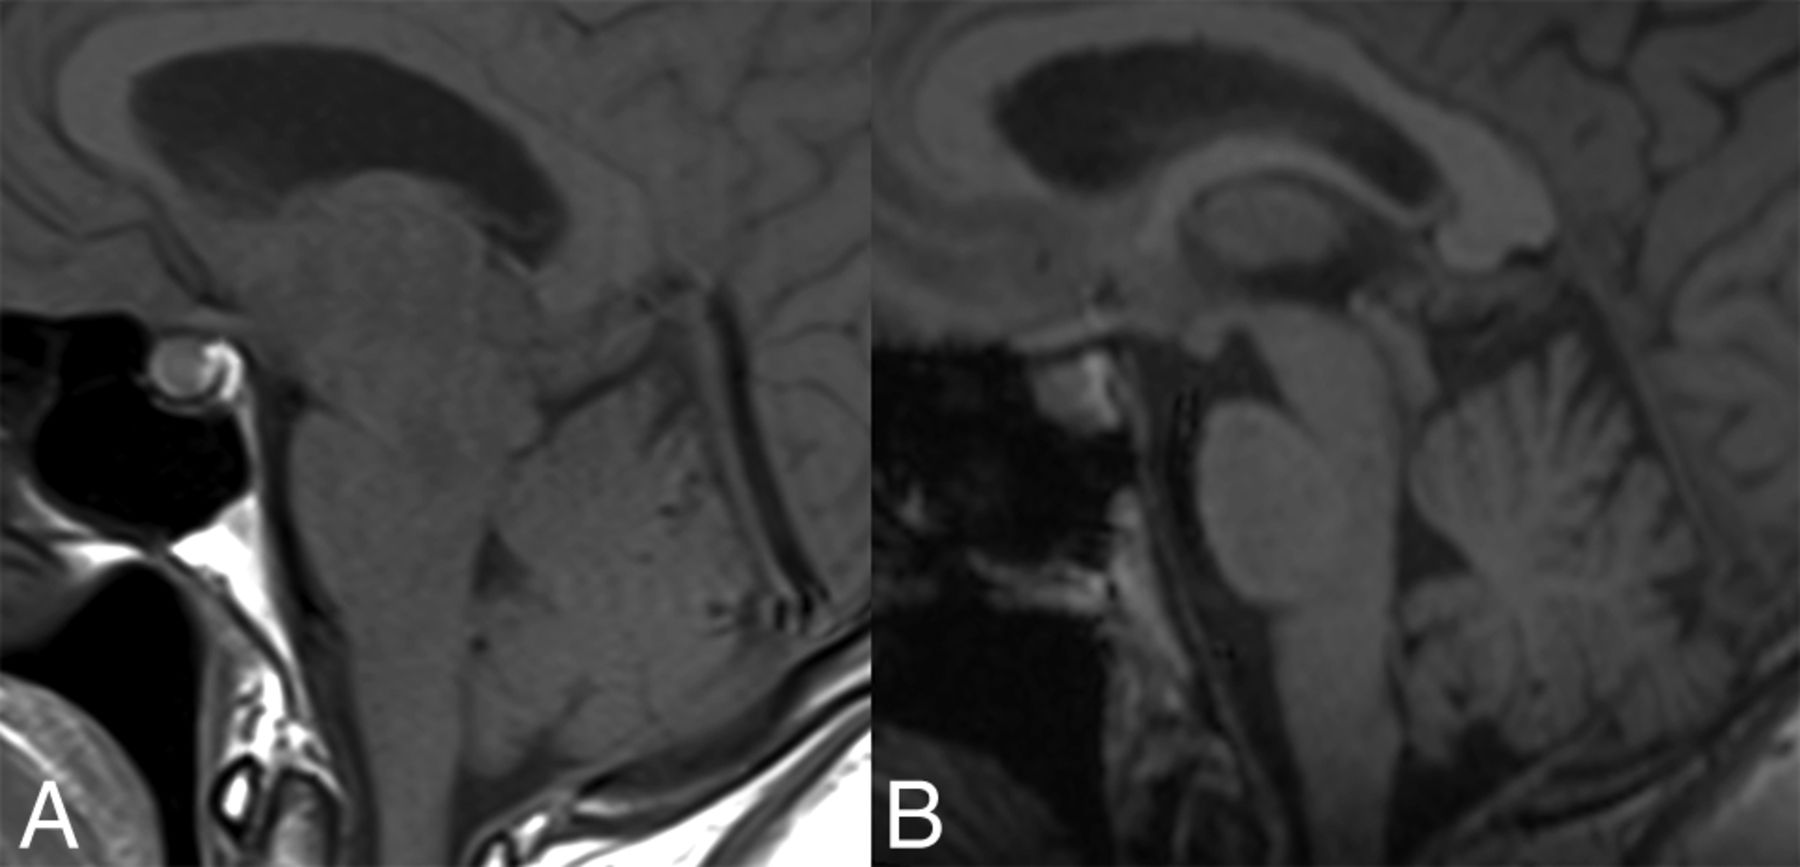

Pre- and posttreatment MRIs of the patient in Fig 2. A, Sagittal T1-weighted MR imaging shows brain sag with narrowing of the mamillopontine distance, narrowing of the prepontine cistern, and inferior sloping of the floor of the third ventricle. There is also pituitary enlargement and distension of the straight sinus. B, Resolution of these changes following CT-guided injection of fibrin sealant.